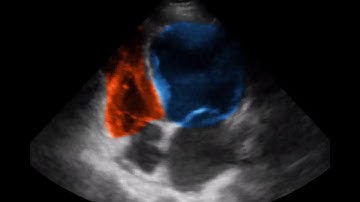

What is the added value of using RV strain?